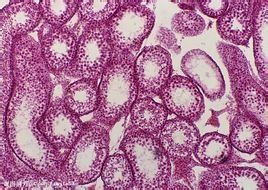

凋亡細胞的主要特徵是(參見表15-2):①染色質聚集、分塊、位於核膜上,胞質凝縮,最後核斷裂,細胞通過出芽的方式形成許多凋亡小體(圖15-4);②凋亡小體內有結構完整的細胞器,還有凝縮的染色體,可被鄰近細胞吞噬消化,因始終有膜封閉,沒有內溶物釋放,故不會引起炎症;③凋亡細胞中仍需要合成一些蛋白質,但是在壞死細胞中ATP和蛋白質合成受阻或終止;④核酸內切酶活化,導致染色質DNA在核小體連線部位斷裂,形成約200bp整數倍的核酸片段,凝膠電泳圖譜呈梯狀;⑤凋亡通常是生理性變化,而細胞壞死是病理性變化。

左,正常胸腺細胞;右,凋亡胸腺細胞如果調節細胞“自殺”的基因出了問題,該死亡的細胞沒有死亡,反而繼續分裂繁殖,便會導致有問題或惡

性細胞不受控制地增長,比如癌症;如果基因錯向不該死的細胞發出“自殺令”,不讓之分裂繁殖,使不該死亡的淋巴細胞大批死亡,便破壞了人體的組織或免疫系統,比如愛滋病。